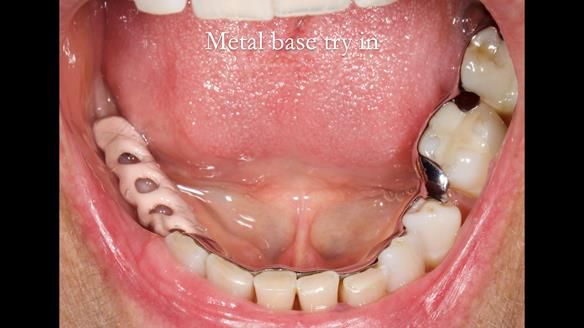

Welcome to Newsletter 61. In this edition, I walk through the process of creating and fitting a metal based lower partial denture for Joyce, a fit and healthy 76 -year-old woman.This issue shows the complete protocol workflow for achieving an exceptionally well-fitted and aesthetically good RPD.

Welcome to Newsletter 61. In this edition, I walk through the process of creating and fitting a metal based lower partial denture for Joyce, a fit and healthy 76 -year-old woman.

The missing lower right teeth to be replaced with a metal based partial denture.

The detailed clinical situation and treatment process are outlined below, with clinical work provided by me and technical work by Rowan Garstang. The treatment spanned six visits for denture fitting and one review.